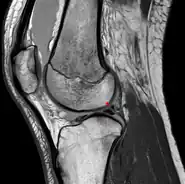

Posterior meniscofemoral ligament (Wrisberg) behind the posterior horn of the lateral meniscus close to its insertion. Sometimes wrongly interpreted as a meniscal tear.